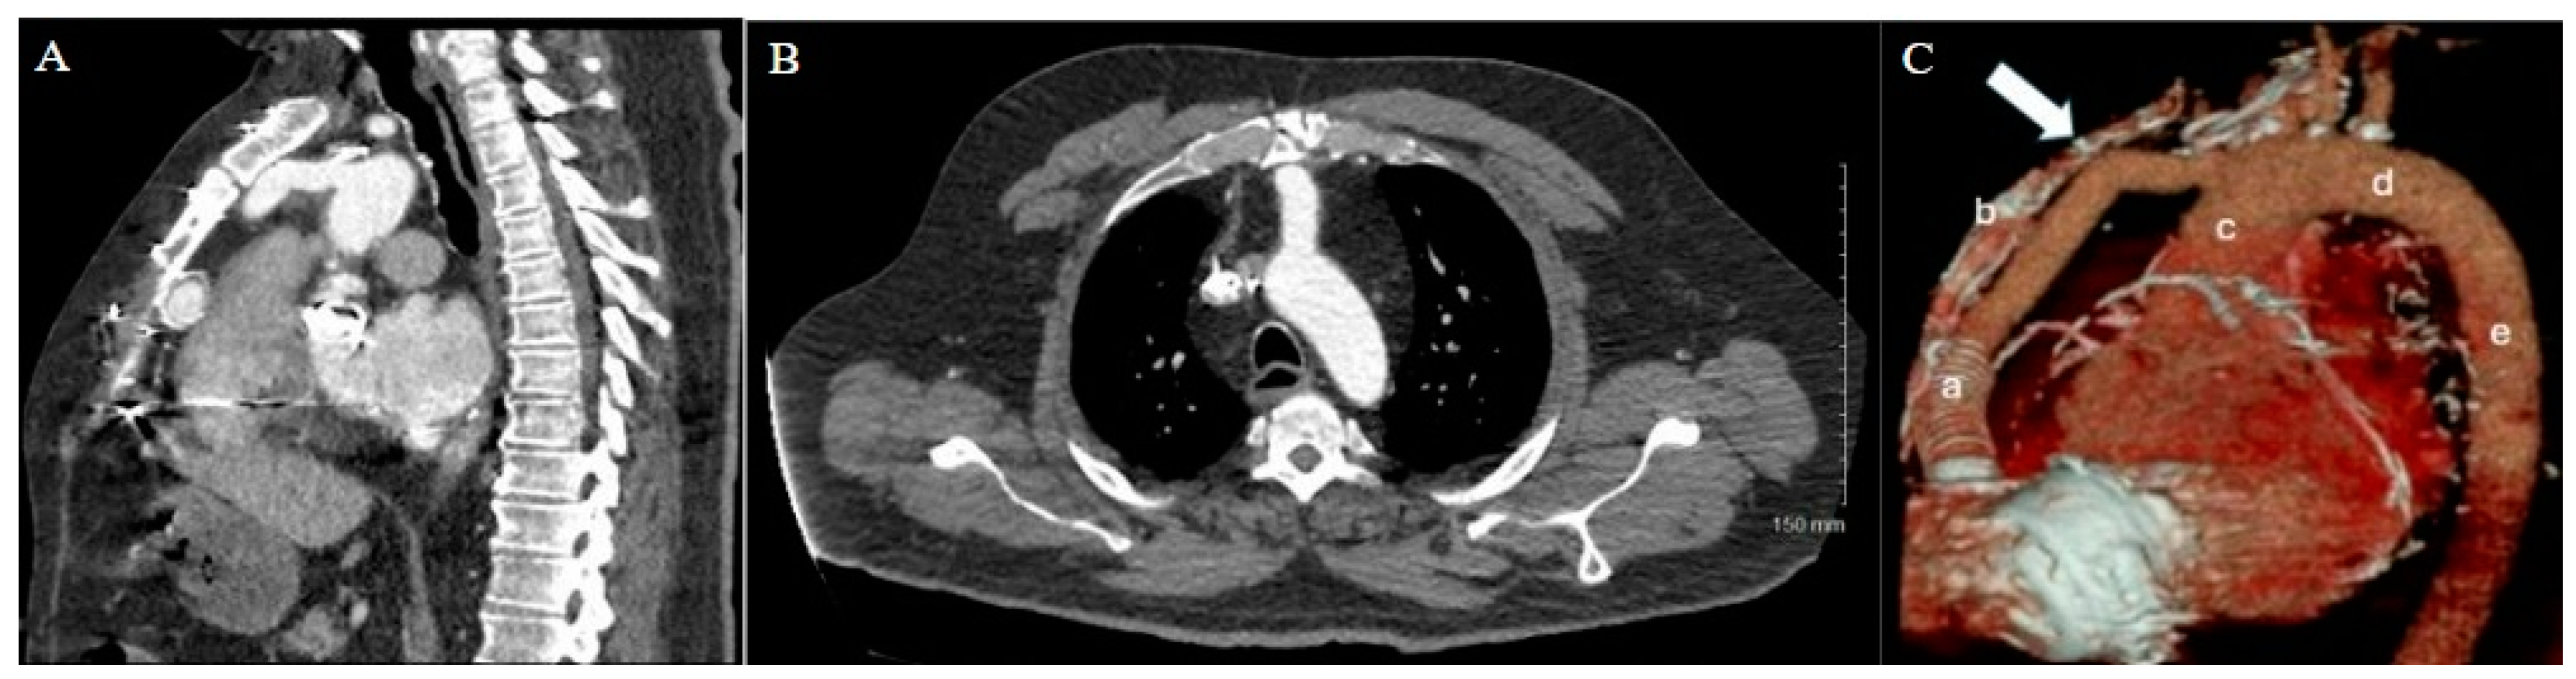

Figure 4. Patient 2 CT chest w/contrast. (A) Sagittal view and (B) axial view reveal extensive adhesions between right atrium and inferior retrosternum.

The patient’s history of repeated sternotomies again created a challenging reentry to the thorax. The preoperative CT revealed extensive adhesions between the right atrium and the inferior retrosternal surface with no pericardium present (Figure 4). Due to multiple previous interventions, the patient did not possess adequate peripheral vessels amenable to cannulation. The two-stage sternotomy approach was again utilized to address these adhesions. A partial sternotomy was initiated at the sternal notch and proceeded inferiorly to the third intercostal space, where an inverted T incision was made (Figure 2B). After the partial sternotomy, the aorta and SVC were carefully dissected and directly cannulated, and CPB was initiated. After CPB was initiated, the stepwise sternotomy was completed with the separation of the remaining inferior portion of the sternum. Due to the dense adhesions between the inferior sternum and the right atrium, the atrium was penetrated by the bone saw and the atrial cavity was directly exposed on opening of the chest. Fortunately, the CPB made for a bloodless field, and direct repair of the right atrial wall with a running Prolene suture was easily achieved. The remainder of the heart was dissected, with cardiectomy and transplantation performed according to standard procedure. The sternotomy was left open until the patient underwent OLT on POD1.

A careful review of the CT imaging was crucial to the preoperative planning of both cases of stepwise sternotomy. The preoperative imaging identified not only structures at risk of reentry injury but also the specific site at which this risk was present. By utilizing landmarks identified in the imaging, we were able to formulate an individualized two-stage approach to reentry that was safe for each patient. With one patient demonstrating inferior retrosternal adhesions and one demonstrating superior retrosternal adhesions, understanding this patient-specific anatomy was necessary to strategize a safe approach to stepwise sternotomy.